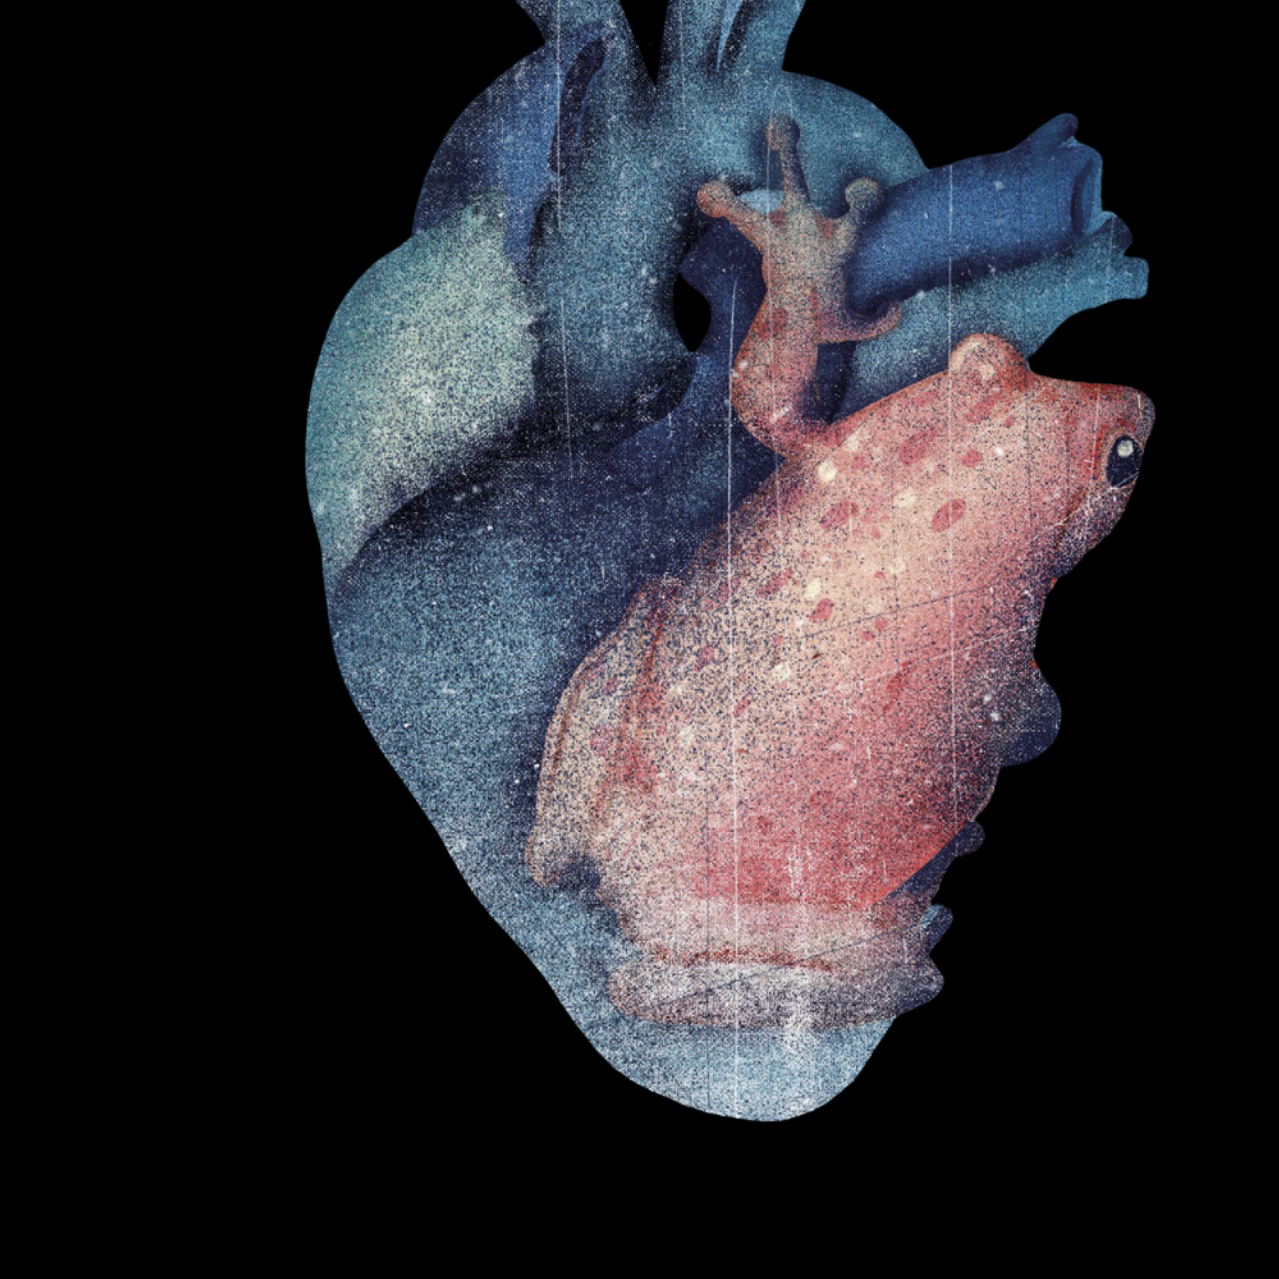

Severe pulmonary edema in a near-SUDEP patient with stereotypical troponin elevations and increased white blood cell counts.

Patients that go into cardiac arrest after a seizure and are successfully resuscitated for at least one hour are said to have experienced a

“near SUDEP”

event. I had such a patient in 2023. She had suffered intermittent epileptic seizures most of her life but never pursued medical care. Thus, she would have met

“probable”

SUDEP criteria had she not been resuscitated. The severity of her pulmonary edema and its correlation with transiently increased white blood cell counts suggest that her seizures triggered a surge of systemic catecholamines

that likely precipitated her sudden and unexpected demise.